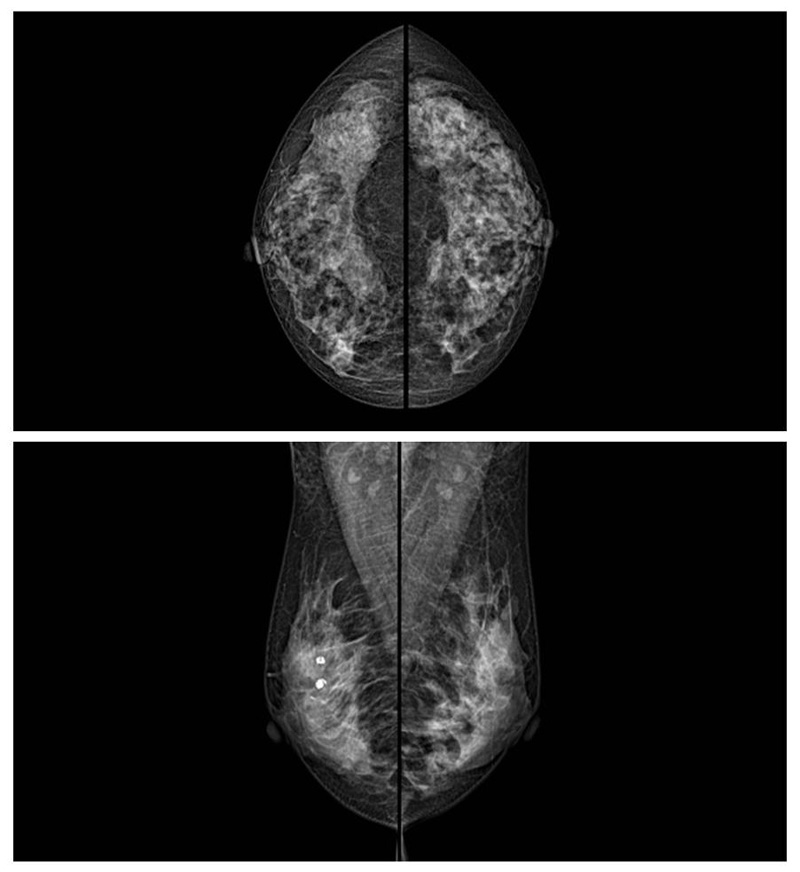

乳腺癌的發(fā)生率越來越高,已經(jīng)是我們國家的癌癥之一已成為女性健康“頭號殺手”。乳腺DR可提高乳腺癌早期檢出率并精準(zhǔn)定位。發(fā)現(xiàn)和診斷早期乳腺癌最有效的方法之一,明顯利大于弊女性都要重視乳腺的檢查。輻射很小最簡便、最可靠、無創(chuàng)性檢查手段,做一次乳腺DR的劑量相當(dāng)于7周的正常生活。尤其是對于40歲以上的女性尤為重要,那么乳腺DR是怎么進(jìn)行檢查的呢?我們來了解一下,為廣大朋友在檢查前有點(diǎn)心理準(zhǔn)備。檢查時(shí)候是避開經(jīng)期的前后,月經(jīng)來后的7天左右比較合適。需要脫衣服檢查,根據(jù)拍片的擺位要求,有頭尾位置,內(nèi)外斜位,還有側(cè)位。定點(diǎn)放大壓迫方法可以更細(xì)微清晰的檢查出病灶。